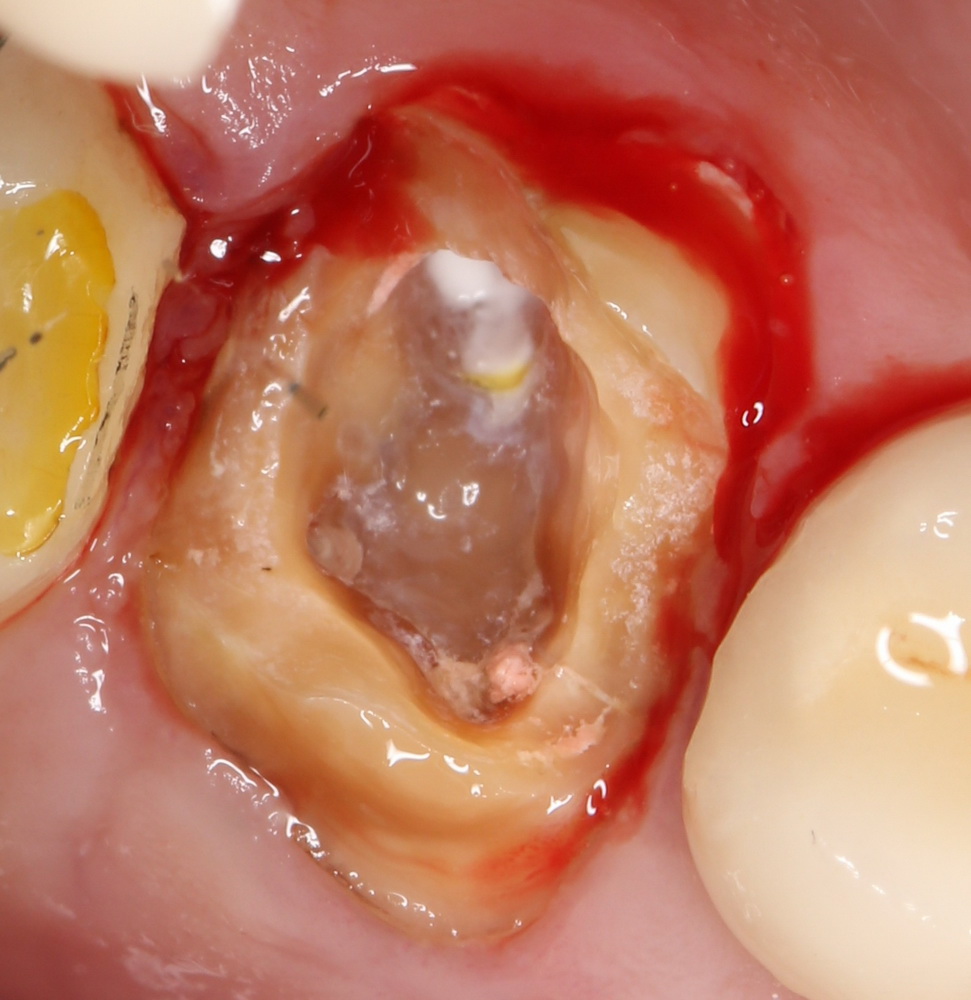

- Обработка лунки?